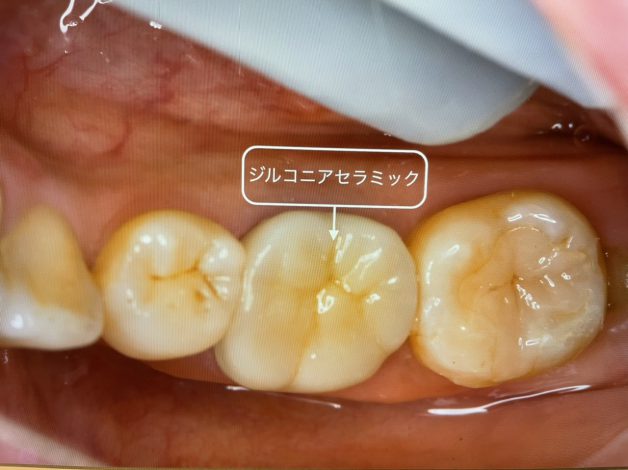

2021/08/26

今日ご紹介するケースは 奥歯が昔のタイプのセラミック 手前がプラスチックが劣化していたケース 共にジルコニアセラミックで作製致しました 型採りも光学印象なので、従来の不快感の強い型採りは不要で…